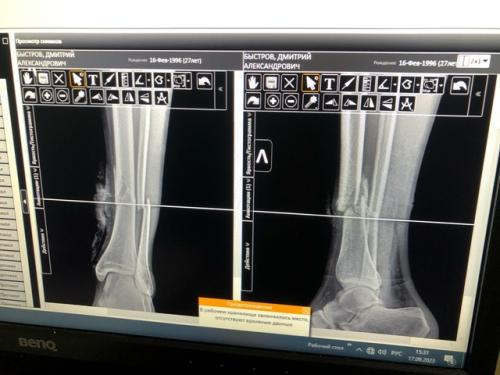

4 9 сентября 2023 муж получает на работе производственную травму. Я вся в слезах еду в мск для того, чтобы перевести мужа в великий - Новгород на операцию. И сама вслед попадаю на операционный стол, по спасению лучезапястного сустава (удаляли гигрому).